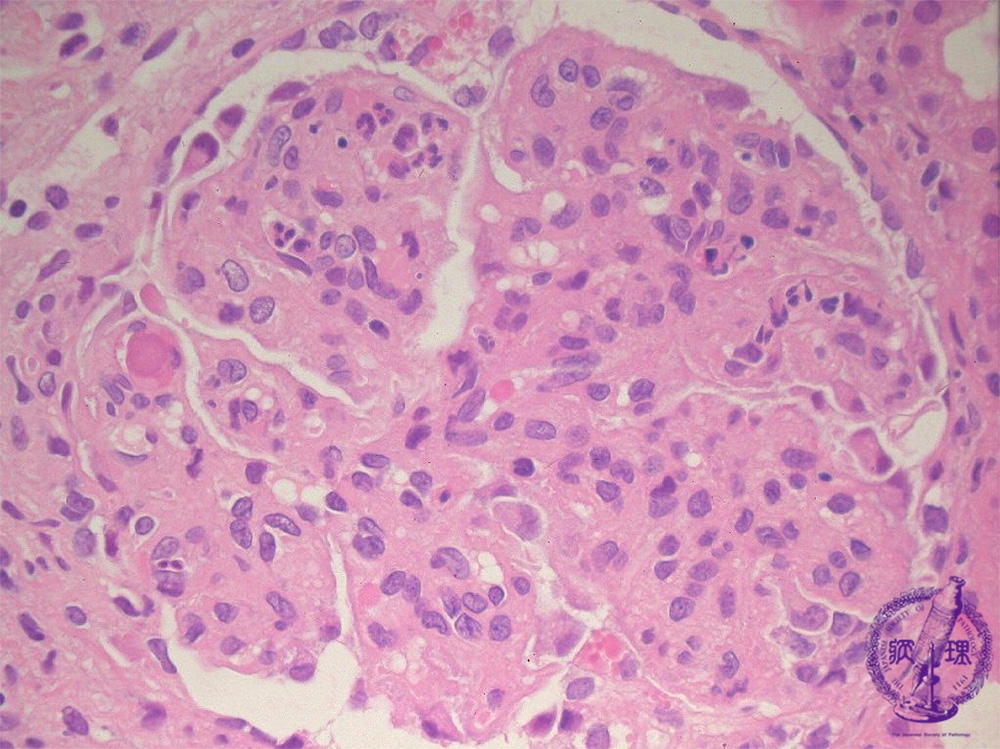

- (6)Lupus Glomerulonephritis

Microscopic findings ( HE, high power view): Lupus nephritis may demonstrate various morphologies; in this picture, the changes are reminiscent of those in membranoproliferative glomerulonephritis. Focally, a hematoxylin body is seen (red arrow).